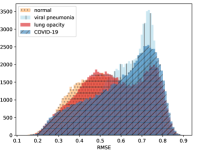

To visualise similarity metrics that compare image pairs (RMSE, SRE, SSIM) two metric distributions are generated: intra-similarity and inter-similarity. For each compared sample 300 random images are selected. The inter-similarity distribution is calculated for each image pair combination from both compared samples e.g. generated images of COVID-19 and real images of COVID-19. For the intra-similarity, all pairs of images in a single sample e.g real images of COVID-19 are considered. By comparing the shape of intra-similarity for the training subsample (Dataset) with the inter-similarity of training and generated samples the quality of the generated sample can be judged. It is also possible to compare in this way between the four image classes present in the dataset. The resulting distributions of inter-similarity of COVID-19 and the three remaining classes are compared in Fig. 4 to distributions of intra-similarity of the COVID-19 sample for each metric. All metrics, as expected based on available medical evidence Rubin et al. (2020), indicate that there are visible differences not only between COVID-19 and normal samples but also between viral pneumonia and lung opacity. Therefore, all classes should be distinguishable.

To visualise differences between synthetic and real samples distributions are generated for each of the RMSE, SRE and SSIM metrics: intra-similarity and inter-similarity. For each compared sample 300 random images are selected. The inter-similarity distribution is calculated for each image pair combination from both compared samples e.g. generated images of COVID-19 and real images of COVID-19. For the intra-similarity, all pairs of images in a single sample e.g real images of COVID-19 are considered. The distributions for generated samples describe very well the distributions for corresponding real images as shown in Fig. 6.